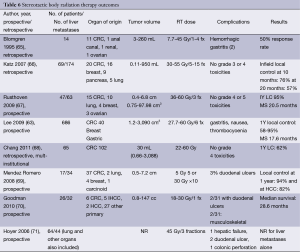

SBRT also known as stereotactic ablative body radiotherapy (SABR) denotes a precise delivery of high doses of radiation to an extracranial target in a small number (usually up to 6) of fractions (63). Standard fractionation of 1.8-2.0 Gray per day is effective because of the differential response of tumor and normal tissue to radiation therapy, with the repeated fractions allowing repair of normal tissues. In contrast, SBRT is thought to be more effective relative to standard fractionation radiation with apparent improvements in tumor cell kill. SBRT is complicated by the need to work with irregularly shaped targets and tumors that are influenced by organ and diaphragm motion. SBRT requires accurate immobilization, a method to manage the respiratory motion of the target, and image guidance to ensure proper alignment and delivery of the radiation dose. Historically SBRT has been used to treat smaller lesions (<6 cm in diameter) in the liver, and it may also be used for larger sized liver metastases as well (63).

SBRT requires careful radiation design with the first step of simulation to create a reproducible position of the patient, using a large rigid pillow conforming to the patient’s external contour with a reference coordinate system beneath and around the patient, which allows for a 3-dimensional localization of the patient. After creating of the immobilization device, a high resolution computed tomography (CT scan) with IV and oral contrast generates an image of the patient, target, and immobilization device. Acquisition of a 4-dimensional CT scan provides information about target and respiratory motion. CT images may be obtained with contrast and can be registered to diagnostic images, such as PET scans or MRIs. During simulation, the method of liver immobilization is determined with options based on institutional availability including controlled breath holds, shallow breathing, abdominal compression devices, beam gating timed to the respiratory cycle, or tumor tracking via implanted fiducial markers (64).

Manual delineation of the target and normal organs by the physician is followed by determination of a beam arrangement to meet specific dose constraints. This process may take several days to generate a highly conformal treatment plan via multiple iterations and discussion between the physician and physics team. Radiation beams may be delivered through a multi-field 3-dimensional conformal plan with a combination of coplanar and non-coplanar beams or intensity modulated radiation therapy (IMRT). To achieve an adequate SBRT plan, numerous beam angles must be employed (6 or more) such that each beam is sufficiently weak to spare radiation dose to normal organs, and at the convergence of the beams, the maximal radiation dose is delivered. Similarly, IMRT employs multiple angles, but within each angle, the shields within the linear accelerator (multileaf collimators) dynamically move to spare organs at risk. IMRT is less ideal for SBRT due to the interplay effect.

During each treatment, assessment of patient position is conducted via image guided radiation therapy, with fluoroscopy, megavoltage or kilovoltage X-rays or cone beam CT scans (CBCT) to assure accuracy of liver positioning. Alternatively, tracking may occur after the placement of fiducials. Although this is a relatively new modality for liver directed therapy, the non-invasive nature of therapy makes it particularly appealing.

Candidates for liver SBRT should have a sufficient performance status (ECOG 0-1) and liver function and no extrahepatic disease. The uninvolved liver volume should be 700 mL or greater (64). Based on the volume of disease, patient comorbidities, baseline liver function, and performance status, the multidisciplinary team can begin to make treatment recommendations for liver-directed therapy. For diffuse disease, the embolization procedures may be appropriate therapy. Although outcomes appear similar in chemo- and radio-embolization, it is important to recognize that the volume of disease in the available literature may be inconsistent. Likewise, most SBRT series allow for larger lesions than RFA despite having apparently similar outcomes (Table 6).